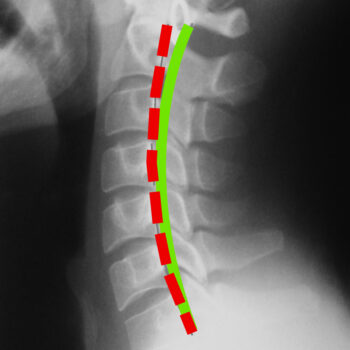

BEFORE

AFTER

Spinal Alignment

Correct posture is at the core of the Chiropractic BioPhysics® method of treatment. The curves in your spine act as levers, shock absorbers, and resistance to gravity; they also protect and reduce forces acting on the spinal cord and nerve tissues. But, gravity, age, poor posture, improper physical activity, injury, and disease can all play a role in the misalignment of your spinal curves and, as a result, your entire body.

Following a scientific analysis of your posture and the curvature of your spine through x-ray and postural analysis software, a treatment plan is developed. Based on your deficits, spinal condition, and other findings, appropriate treatment will be prescribed to restore proper alignment, relieve pain, and improve function.